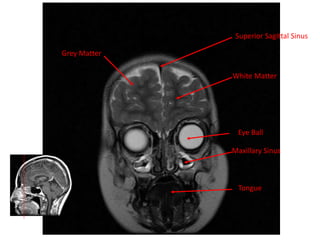

Grey Matter

Superior Sagittal Sinus

White Matter

Eye Ball

Maxillary Sinus

Tongue